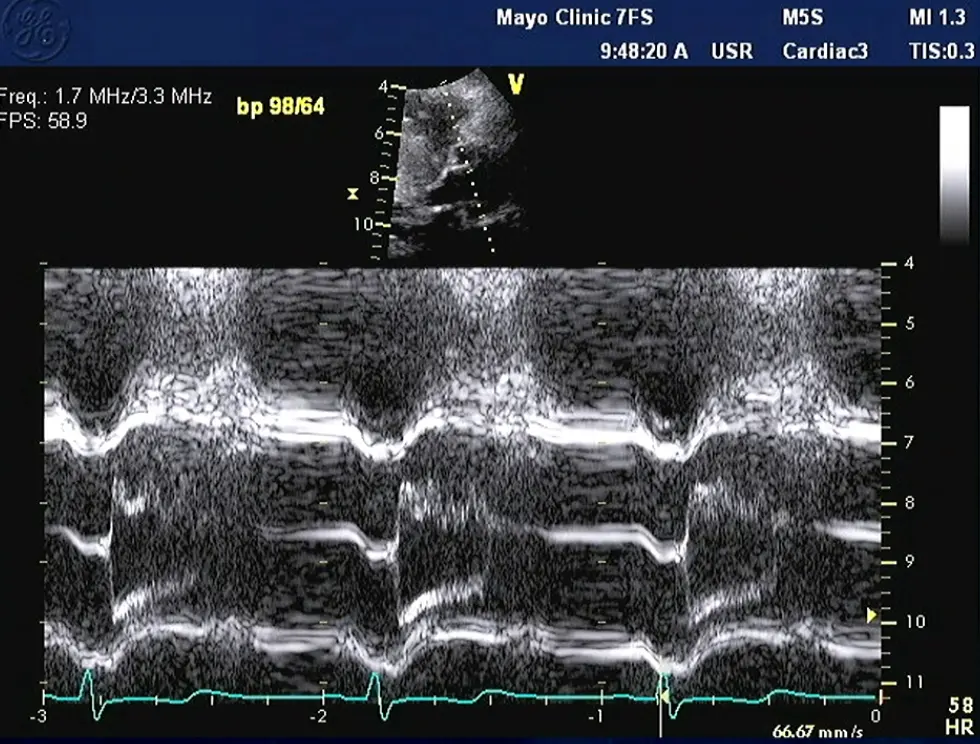

M-mode

- Temporal resolution of M-mode → the duration of SAM where it is in contact with the septum correlates w/ severity of LVOT obstruction

- M-mode in the parasternal long-axis view may assess for midsystolic notching of the aortic valve, reflecting very rapid ejection of LV stroke volume in early systole followed by attenuation of stroke volume in the obstructive phase.

Notice the turbulence, which suggests LVOTO